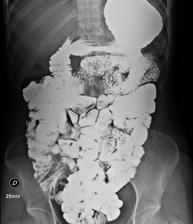

- RX Abdomen

Técnica mediante la cual, utilizando rayos X, se obtienen imágenes del abdomen (estómago, intestino delgado, intestino grueso, hígado, riñones, vejiga, pelvis ósea, etc.) para su estudio.

Una radiografía de abdomen es una técnica mediante la cual, utilizando una pequeña dosis de radiación, se obtiene una imagen bidimensional del abdomen con sus estructuras anatómicas (estómago, intestino delgado, intestino grueso, hígado, páncreas, riñones, vejiga, pelvis ósea, etc.).